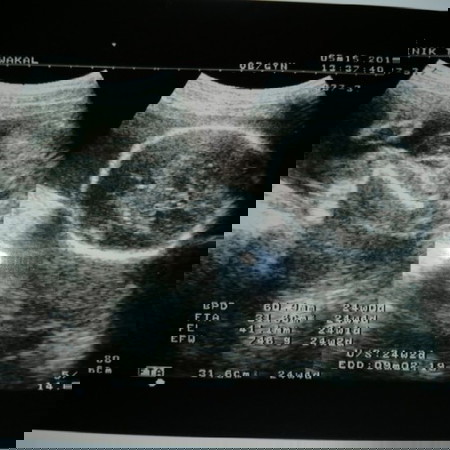

Usg Scan

Alhamdulillah baru lepas scan baby.. Bakal dapat baby boy.. ?